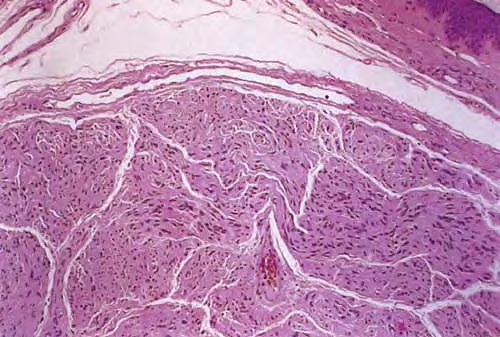

Palisaded encapsulated neuroma = الورم العصبي المحاط بمحفظة وسياج